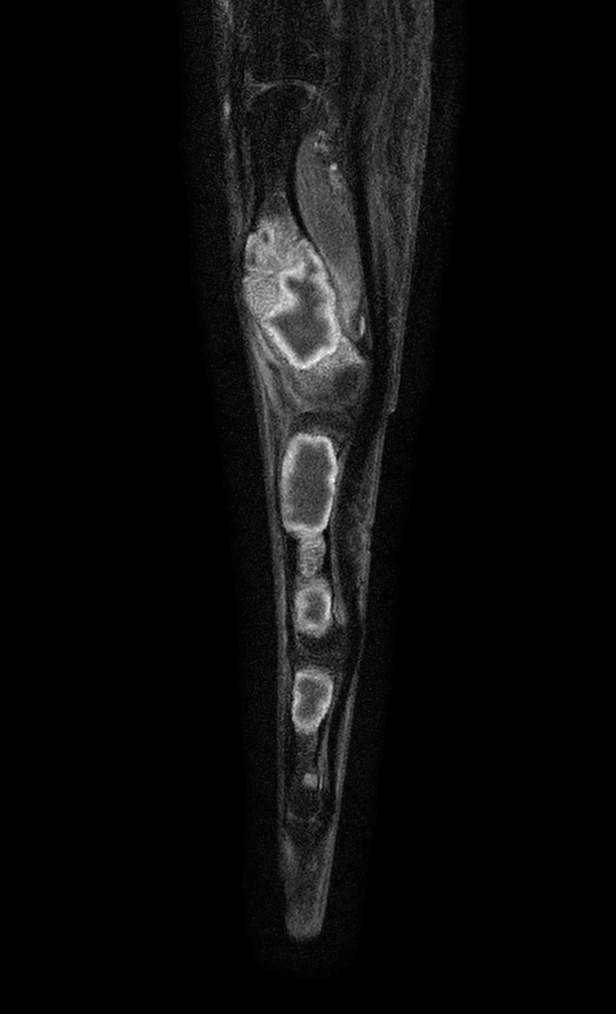

Sagittal T1w mDIXON XD TSE (Water only) (with gado)

Sagittal T1w mDIXON XD TSE (In Phase) (with gado)

Sagittal T1w mDIXON XD TSE (Partial FatSat) (with gado)